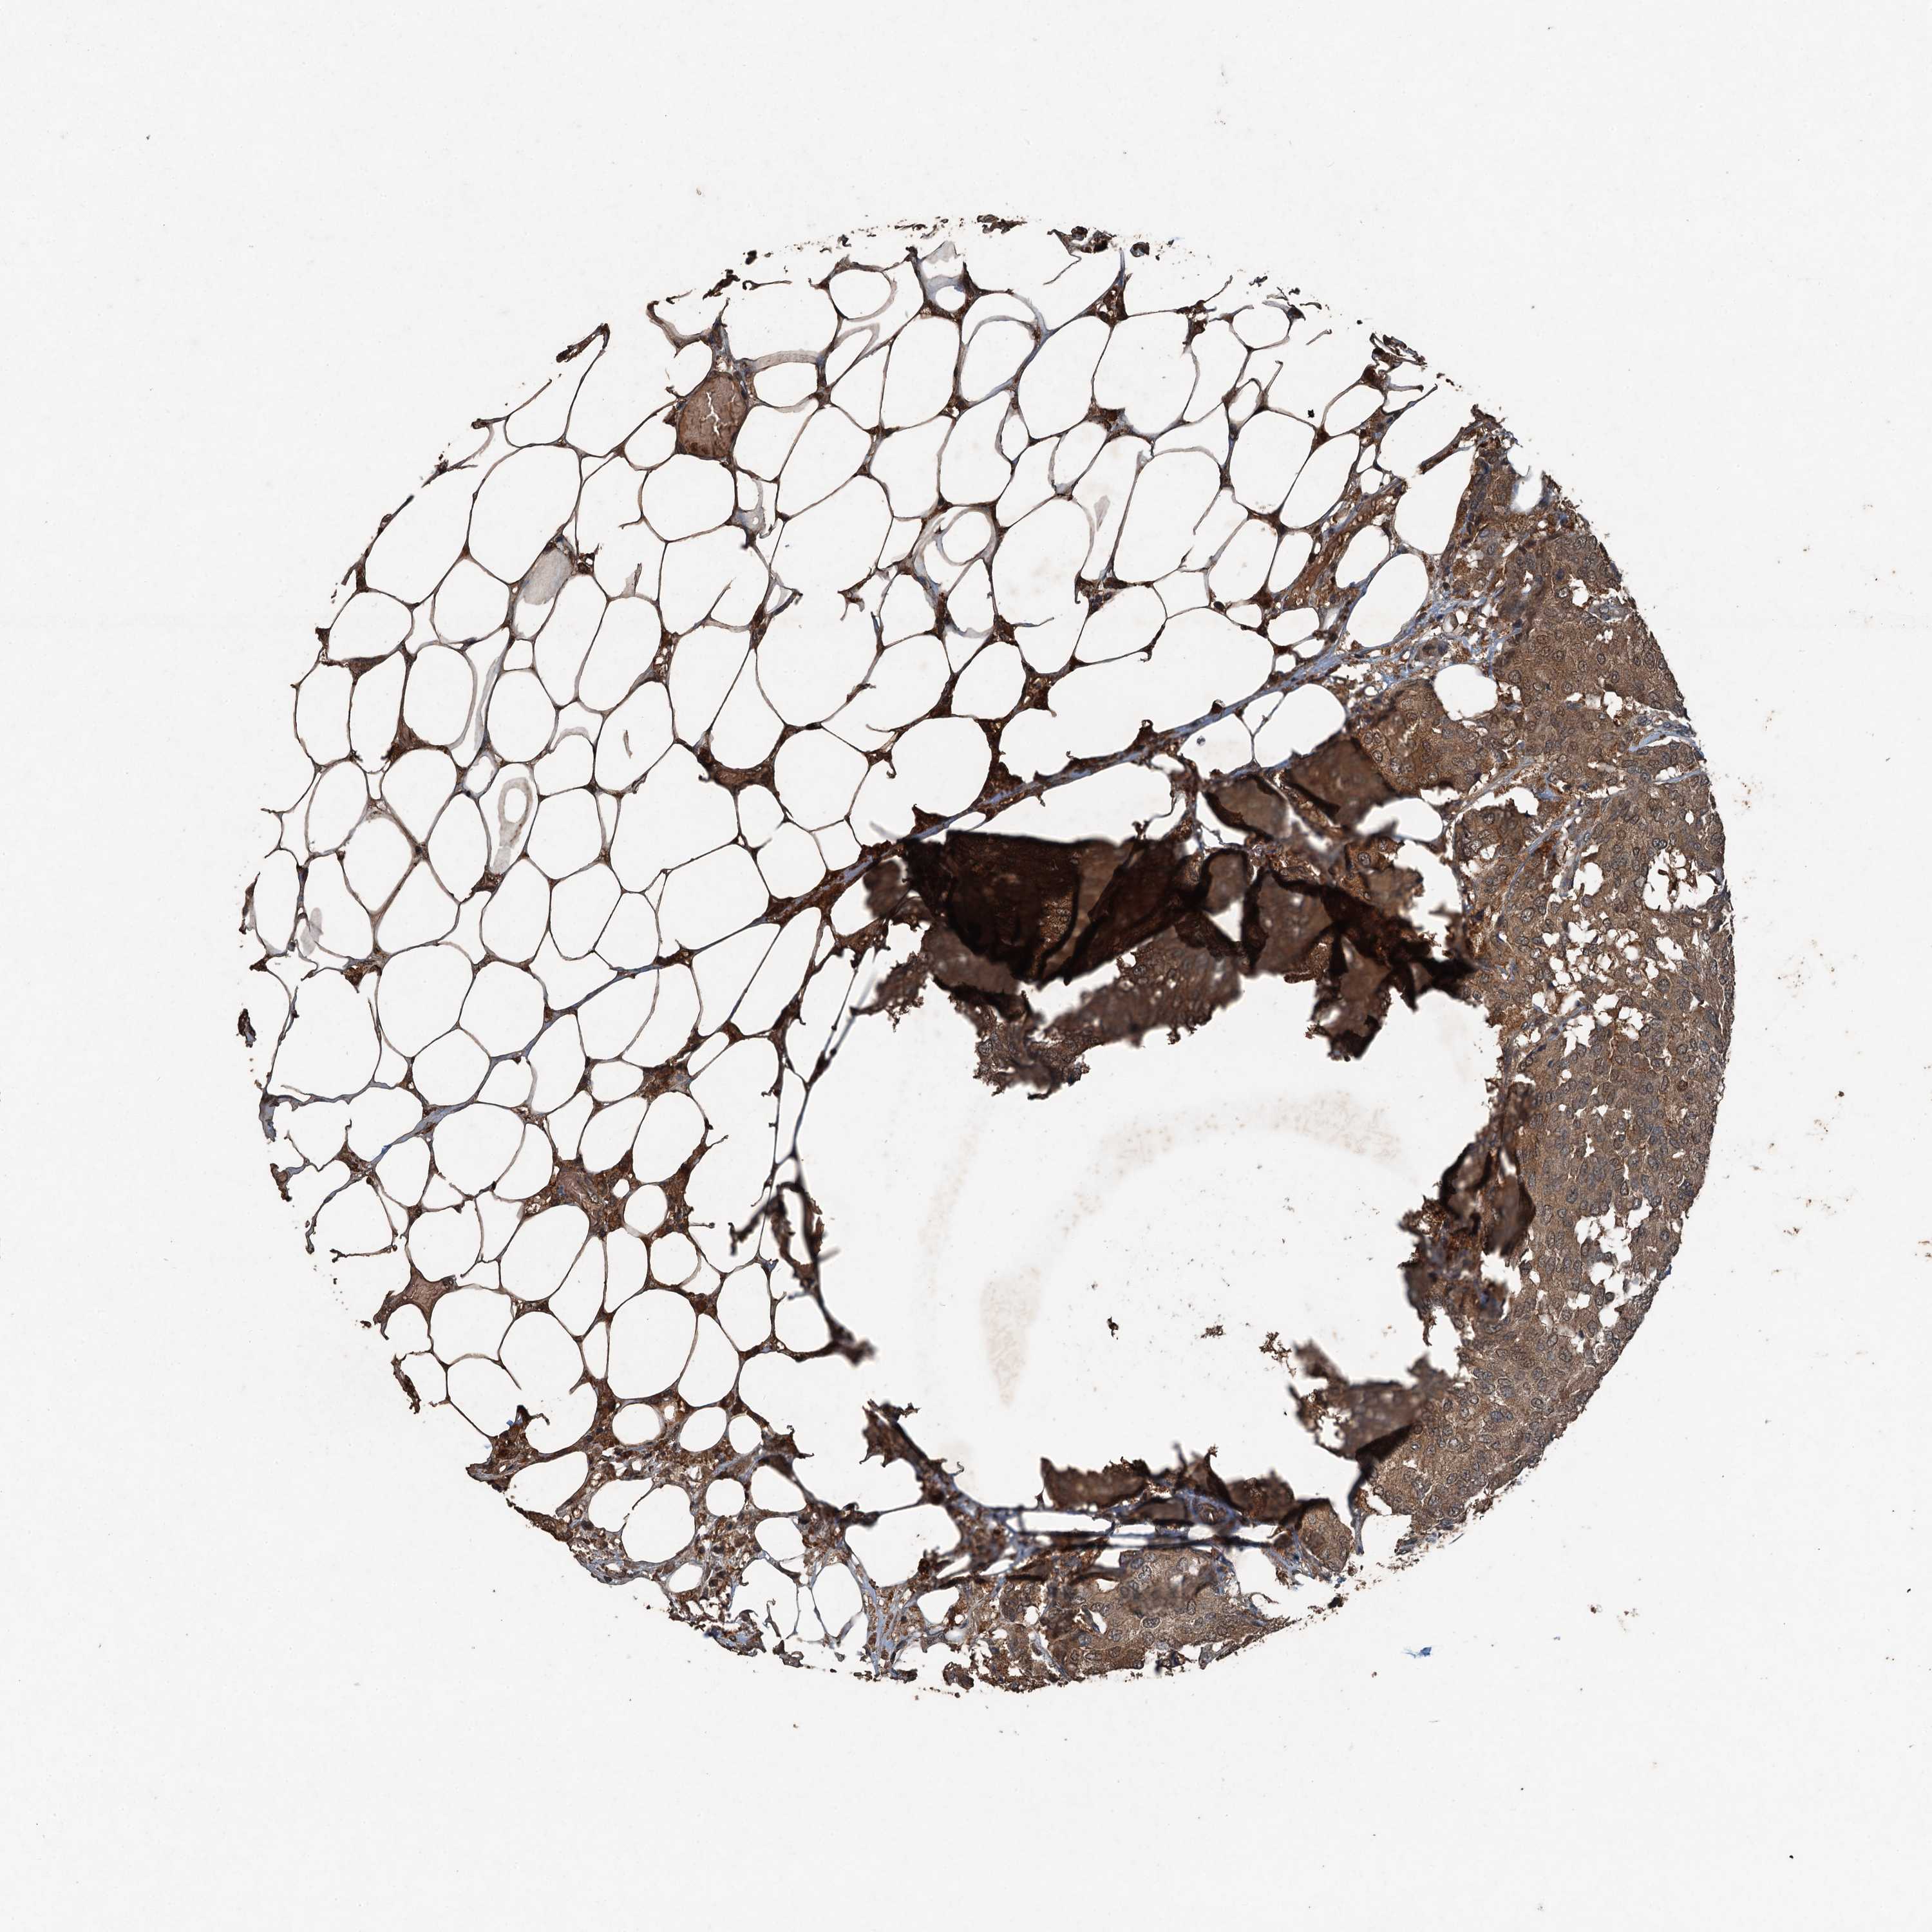

CANCER BREAST CANCER Show tissue menu

BRCA TCGA BRCA VALIDATION PROTEIN EXPRESSION